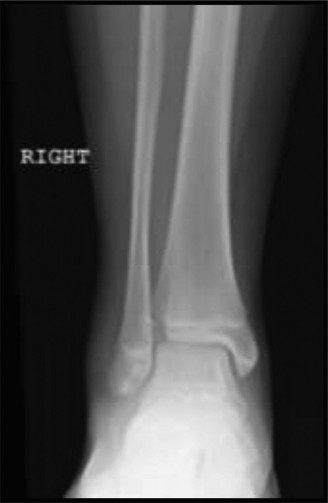

Tillaux fragment. Coincidentally, a 13-year-old male (a player for the opposing team) is in the next bed in the emergency room, awaiting evaluation of a left ankle injury that was sustained in a similar fashion later in the game. Upon your evaluation, his skin is closed, his foot and ankle are swollen, and he is able to actively flex and extend his toes with minimal discomfort. His initial radiographs are shown ( Fig. 10–15A C ). Based on the available imaging you diagnose this patient with a** ** (choose the correct group of answers).

Figure 10–15 A–B

Figure 10–15 C

1. Triplane fracture; Salter–Harris III on sagittal view; Salter–Harris II on anteroposterior (AP) view

2. Triplane fracture; Salter–Harris II on sagittal view; Salter–Harris III on AP view

3. Triplane fracture; Salter–Harris III on sagittal view; Salter–Harris III on AP view

4. Tillaux fracture; Salter–Harris III on sagittal view; Salter–Harris II on AP view

5. Tillaux fracture; Salter–Harris II on sagittal view; Salter–Harris III on AP view

Discussion

The correct answer is (B). Classically, triplane fractures have the radiographic appearance of a Salter–Harris II fracture on lateral radiographs and of a Salter–Harris III fracture (this is the Tillaux fragment) on coronal imaging.